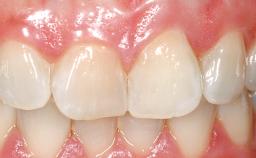

A 42-year-old female patient was referred to our clinic at the School of Dentistry of the University of São Paulo in November 2004, presenting a deficient restoration in the upper left central incisor. The clinical examination revealed no gingival retraction or any signs of gingival inflammation and, therefore, previous periodontal treatment was not considered. The patient presented a high lip line at full smile and a thin tissue biotype. This combination characterized a high-risk situation from an anatomic point of view, which required careful preoperative planning and cautious surgical execution.

Lip Line No exposure of papillae Exposure of papillae Full exposure of mucosa margin

Periodontal Phenotype Low-scalloped, thick Medium-scalloped, medium-thick High-scalloped, thin